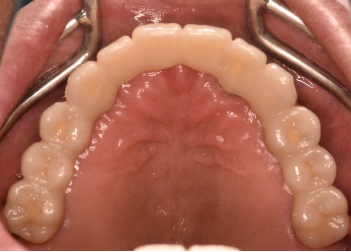

男性Kさん 50代(インプラント)

主訴

歯がグラグラするところ、むし歯のところ、しみるところ、被せ物がとれたところ、歯茎が腫れて血が出るところ、歯が抜けているところがある。すべて治したい。

治療内容

残っている歯を抜歯し、上下インプラント治療をしました。

所感

歯周病が進行している歯、むし歯が進行している歯がほとんどで、レントゲンを撮り、詳しく診てみると、ほとんどの歯を保存することができないことがわかりました。抜歯後は、入れ歯かインプラントの方法があります。治療開始前に患者さんに詳しく現状を説明し、治療法についてじっくり相談しました。自分の歯と同じような感覚で食事できるインプラント治療を選択されました。治療後、表情がとても明るくなり、口元がとても自然で10歳以上若返ったように感じました。「時間はかかりましたが、インプラントにして本当に良かったです!」と素晴らしい笑顔でお話ししてくださいました。

上顎:¥3,280,000(税込)

下顎:¥3,280,000(税込)